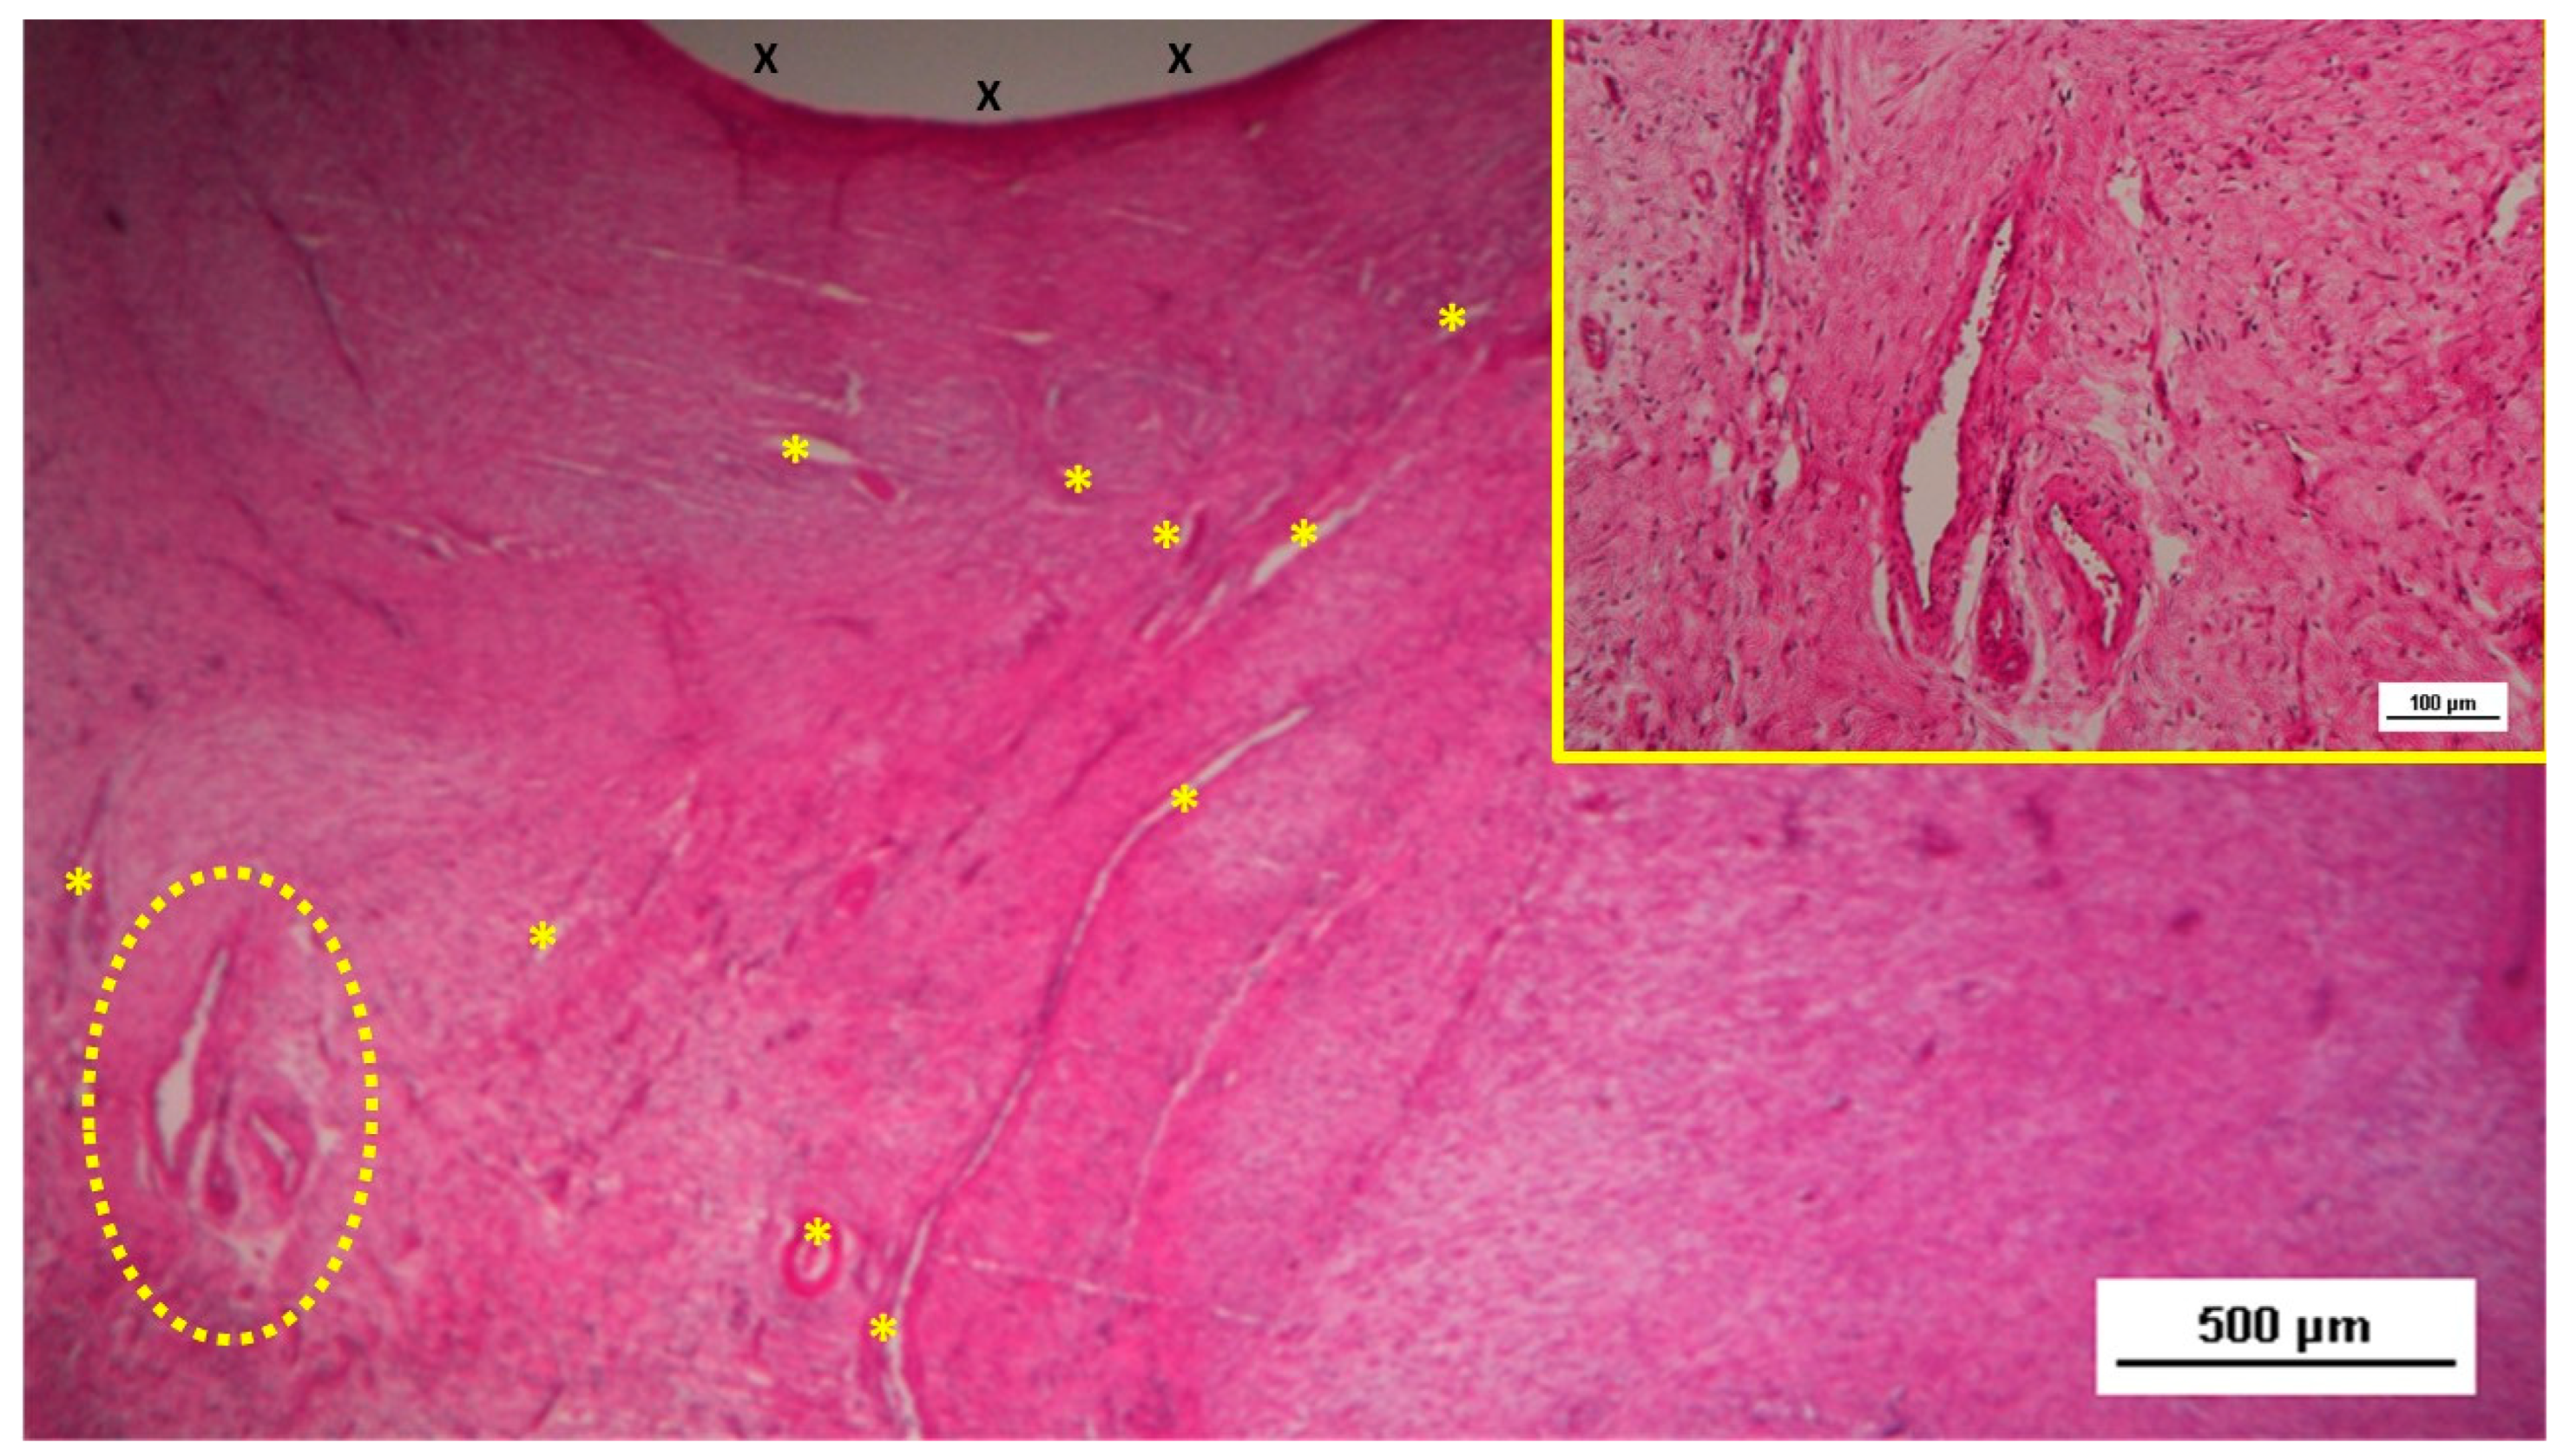

- Amato, G.; Puleio, R.; Romano, G.; Calò, P.G.; Di Buono, G.; Cicero, L.; Cassata, G.; Goetze, T.; Buscemi, S.; Agrusa, A.; et al. Physiologic Cyclical Load on Inguinal Hernia Scaffold ProFlor Turns Biological Response into Tissue Regeneration. Biology 2023, 12, 434. [Google Scholar] [CrossRef] [PubMed]

- Amato, G.; Romano, G.; Puleio, R.; Agrusa, A.; Goetze, T.; Gulotta, E.; Gordini, L.; Erdas, E.; Calò, P. Neomyogenesis in 3D Dynamic Responsive Prosthesis for Inguinal Hernia Repair. Artif Organs. 2018, 42, 1216–1223. [Google Scholar] [CrossRef]

- Amato G, Agrusa A, Puleio R, Calò PG, Goetze T, Romano G Neo-nervegenesis in 3D dynamic responsive implant for inguinal hernia repair. Qualitative study. International Journal of Surgery 2020, 76, 114–119. [Google Scholar]

- Amato, G.; Puleio, R.; Rodolico, V.; Agrusa, A.; Calò, P.G.; Di Buono, G. Romano G, Goetze T. Enhanced angiogenesis in the 3D dynamic responsive implant for inguinal hernia repair ProFlor®. Artif Organs. 2021, 00, 1–10. [Google Scholar]

- Amato G, Agrusa, Puleio R, Micci G, Cassata G, Cicero L, Di Buono G, Calò PG, Galia M, Romano G. A regenerative scaffold for inguinal hernia repair. MR imaging and histological cross evidence. Qualitative study. Int J Surg. 2021, 96, 106170. [Google Scholar]